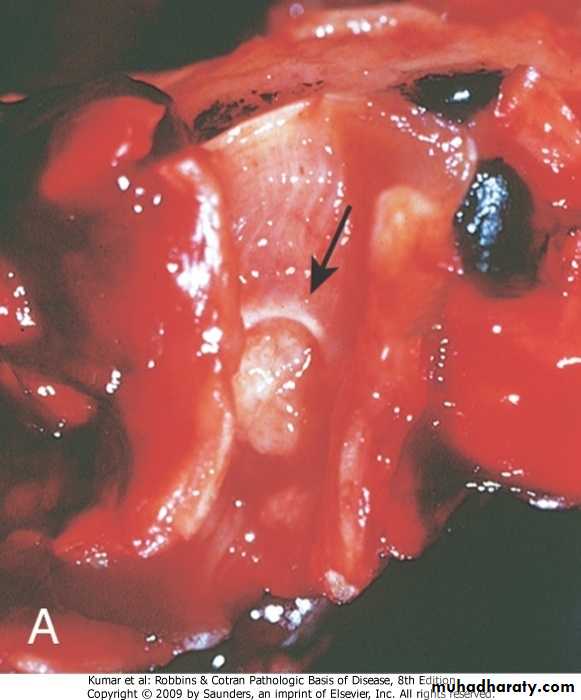

Bronchogenic carcinoma

Respiratory  System

Pathology of bronchogenic carcinoma

Site:

1.Central 55% arises from main bronchus

2. Perpheral 40 % arises from small bronchi and bronchiole

Diffuse 5%

Pathology of bronchogenic carcinoma (cont)

Histopathological classification:

1. Squamous cell carcinoma ; arises from squamous metaplastic epithelium---dysplasia---carcinoma in situ---invasive carcinoma.

It is usually poorly differentiated